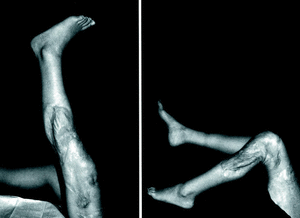

Al año de seguimiento, en las radiografías se observó la incorporación progresiva del extremo óseo del injerto (fig. 3). La paciente camina sin ortesis y sin bastones, existiendo atrofia del cuádriceps y un balance articular activo de 0-120° (fig. 4); el injerto de tendón rotuliano se puede palpar subcutáneamente, al igual que las agujas de Kirshner del obenque rotuliano.

Figura 4. Resultado clínico al año de la intervención con extensión activa completa y 120° de flexión.